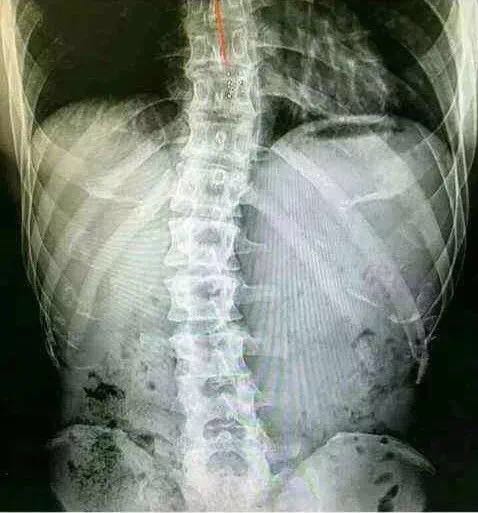

*钟金**国很早就患有脊柱侧弯,这种病发作起来非常痛苦,他一直咬紧牙关的健身,很大一部分原因就是想练出肌肉来支撑弯曲的脊柱,这是一个为了活着而运动的男人。

*钟金**国晒自己脊柱侧弯照片